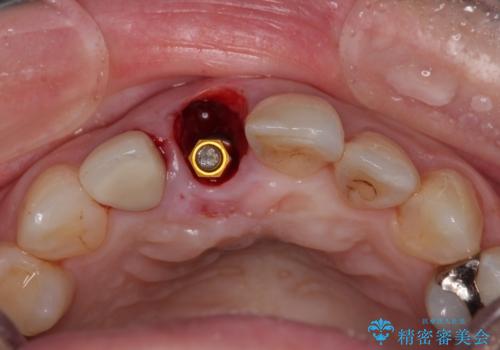

- 前歯のデコボコと変色した前歯を気にして来院された患者様です。

抜歯矯正により口元を引っ込めることも検討しましたが、特に口元の突出感は気になっていないとのことで、非抜歯にてワイヤー装置で矯正治療を行うこととしました。

気になっていた前歯の変色も、矯正治療後にオールセラミッククラウンにて補綴治療を行うこととしました。